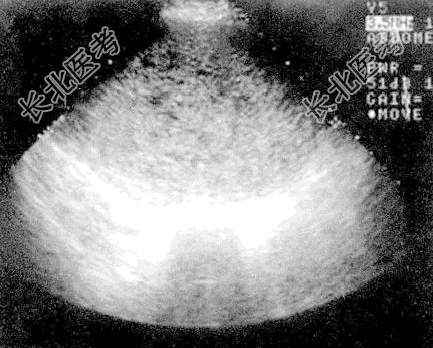

- [材料题] 女性,31岁,阴道流血1月余,妇科检查子宫孕5个月大小,质软,声像图见图。

- 多项选择题3.该患者超声检查结果为:子宫明显增大, 14.7cm×10.8cm×10.4cm,宫内见杂乱低回声并大小不等囊性结构, 可见片状无回声区,CDFI可探及低阻动脉血流。宫壁回声不清。双附件区未见异常。未见腹水。其最有诊断价值的检查项目是